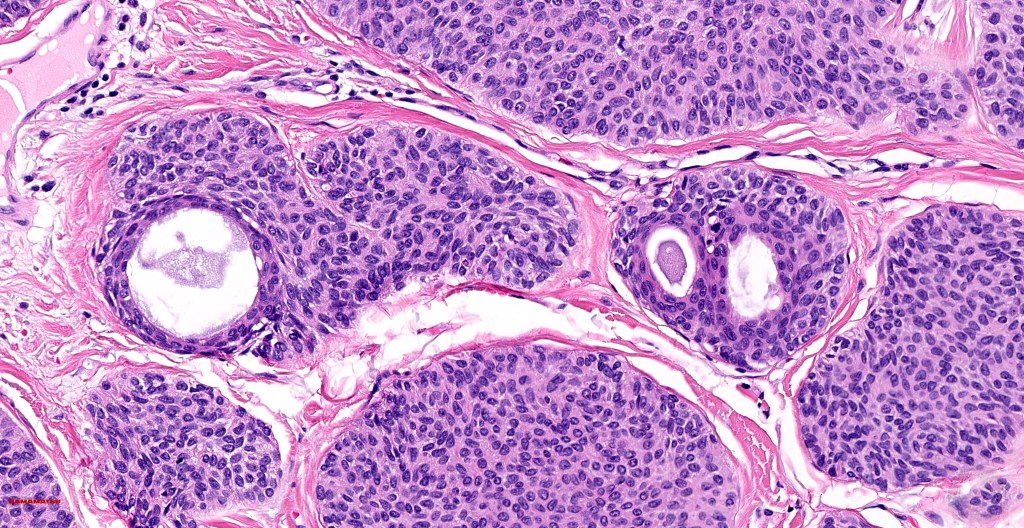

•Dermal duct tumor comprises dermal nodules composed of poroid cells showing ductal differentiation & intracytoplasmic lumina with variable cyst formation

•In poroma, a dermal-centric tumor is associated with epidermal origin/continuity & is composed of small cells with vesical nuclei.

•Desmosomes often prominent

•No peripheral palisading or retraction artifact

•Variable squamous differentiation (can be marked)